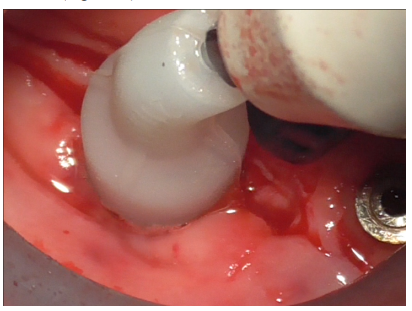

A healing abutment was then screwed into the implant to preserve the connection during subsequent stages (Figure 21).

Figure 21

Additional decontamination was performed with the previously used diamond ball insert for the Ultrasonic Device (Figure 22).

Figure 22